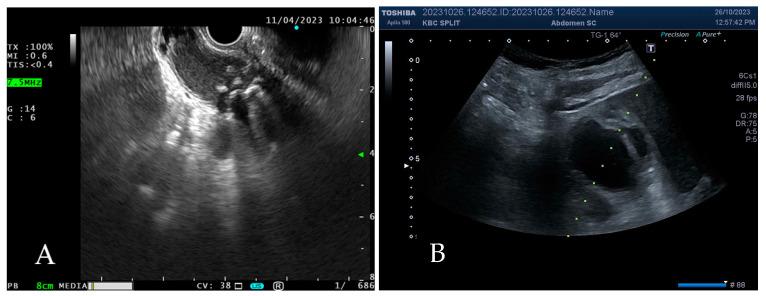

Gallbladder drainage is a treatment option in high-risk surgical patients with moderate or severe acute cholecystitis. It may be applied as a bridge to cholecystectomy or a definitive treatment option. Apart from the simple and widely accessible percutaneous cholecystostomy, new attractive techniques have emerged in the previous decade, including endoscopic transpapillary gallbladder drainage and endoscopic ultrasound-guided gallbladder drainage. The aim of this paper is to present currently available drainage techniques in the treatment of AC; evaluate their technical and clinical effectiveness, advantages, possible adverse events, and patient outcomes; and illuminate the decision-making path when choosing among various treatment modalities for each patient, depending on their clinical characteristics and the accessibility of methods.

胆囊引流是高危手术患者中、重度急性胆囊炎的一种治疗选择。它可作为胆囊切除术的桥梁或一种确定性治疗选择。除了简单且广泛应用的经皮胆囊造瘘术外,在过去十年中还出现了新的有吸引力的技术,包括内镜经乳头胆囊引流术和内镜超声引导下胆囊引流术。本文的目的是介绍目前治疗急性胆囊炎可用的引流技术;评估其技术和临床有效性、优点、可能的不良事件及患者预后;并阐明根据每位患者的临床特征和方法的可及性,在为每位患者选择各种治疗方式时的决策路径。